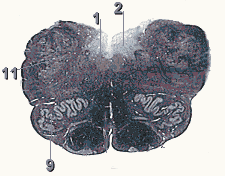

На поперечном срезе, проведенном через оливы (oliva) (см. рис. 1), в последних различают скопления серого вещества. Наибольшее из них, нижнее оливное (nucleus olivaris inferior) или зубчатое ядро (nucleus dentatus), имеет складчатую форму. Также в оливах можно различить ядра меньшего размера: медиальное добавочное ядро оливы (nucleus olivaris accessorius medialis) и дорсальное добавочное ядро оливы (nucleus olivaris accessorius dorsalis). На дорсальную область среза проецируются ядра VII-XII пар черепных (черепно-мозговых) нервов. В медальной части среза видна ретикулярная формация (formatio reticularis) – сетчатое образование, состоящие из множества островков серого вещества, отделенных друг от друга белыми волокнами.

Рис.1 Поперечный срез спинного мозга.

1. Nucleus hypoglossus

2. Nucleus dorsalis vagi

9. Oliva

11. Nucleus tractus spinalis nervi trigemini